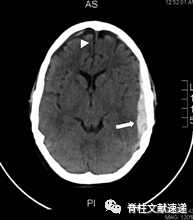

图注:40岁女性,既往多次腰椎手术史,再行翻修手术中发现发现硬膜缺损并给予修复。术后三周,病人出现进行性头痛。腰椎磁共振成像显示术区积液。再次手术探查,但未见渗漏。患者头痛持续,术后24小时进行CT扫描,显示右侧硬脑膜下血肿(SDH),中线移位。病人接受紧急颅骨切开引流减压。随访CT显示SDH恢复良好。

图注:55岁女性,腰椎翻修手术硬膜撕裂,术后第7天出现神经系统变化(神志错乱、失语等)。头颅CT示左侧额叶、顶叶、颞叶有硬膜下血肿,中线移位。患者被紧急送至手术室进行硬膜下血肿的清除。手术后失语症完全消失,头颅CT显示左侧血肿完全清除。